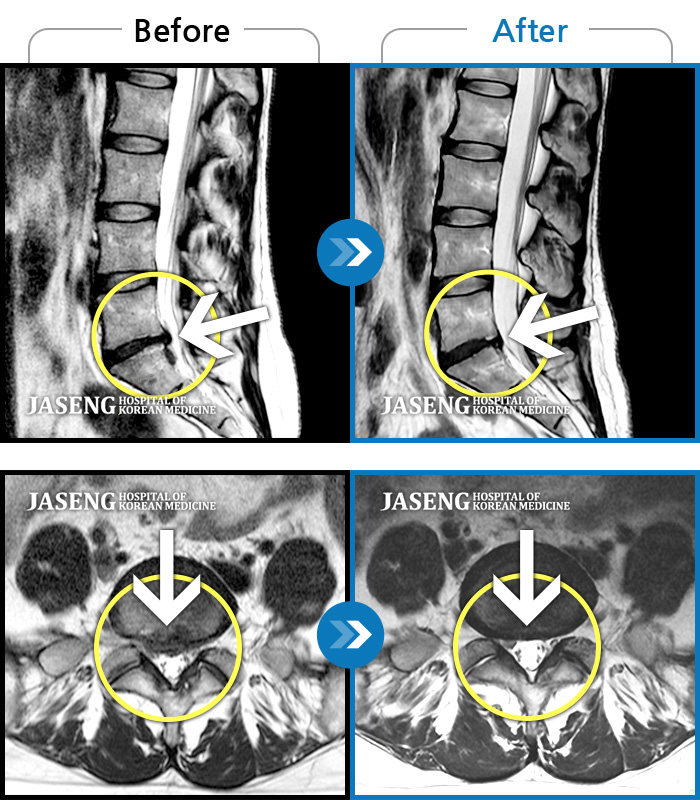

허리디스크

광주 · 이영식 원장

허리 통증과 우측 허벅지 통증 및 저림 증상 지속되어 내원하셨습니다.

촬영시기

2022.08.20 ~ 2024.11.08